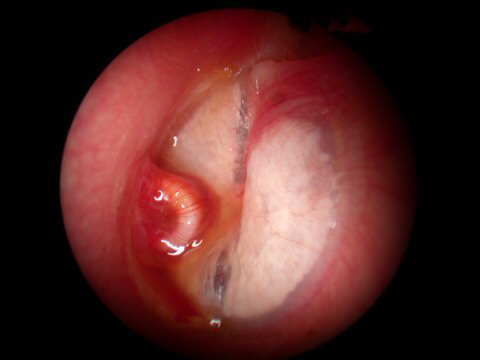

Notice the different shades of color yet the eardrum still remains an opaque translucent appearance in all the pictures

Acute Infection with bulging of the tympanic membrane due to pressure from purulence (pus) behind it. The last picture reveals an ear tube that has gotten prematurely blocked and the ear is once again infected.